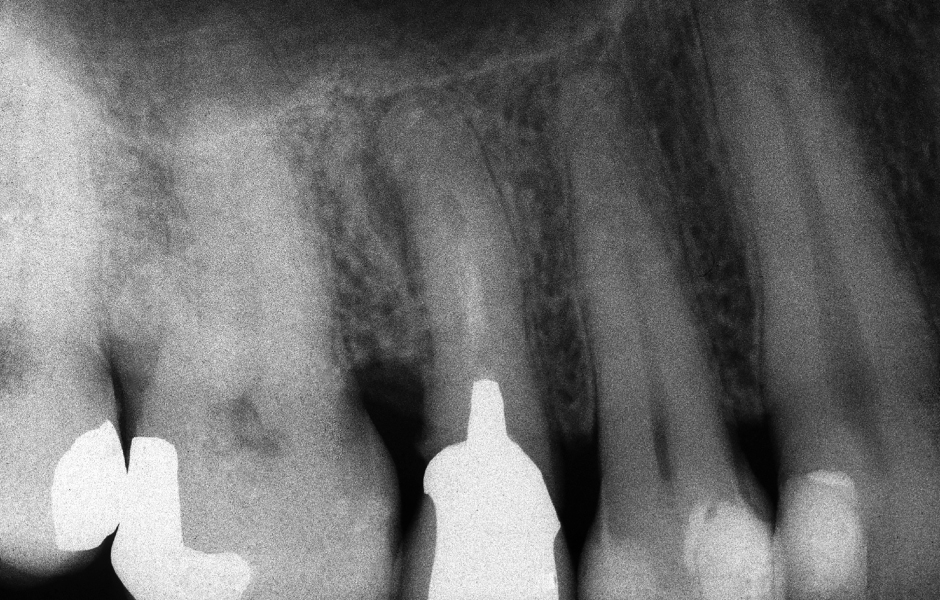

Obr. 1.1: Předoperační rentgenový snímek horního pravého středního řezáku.

Obr. 2.1: Předoperační rentgenový snímek horního pravého druhého moláru. Je patrná drobná laterální radiolucence indikující přítomnost laterálního kanálku.

Obr. 4.1: Předoperační snímek horního levého prvního moláru. Oba kanálky mesiobukálního kořene byly kompletně kalcifikované a nebylo možné je ortográdně zprůchodnit.